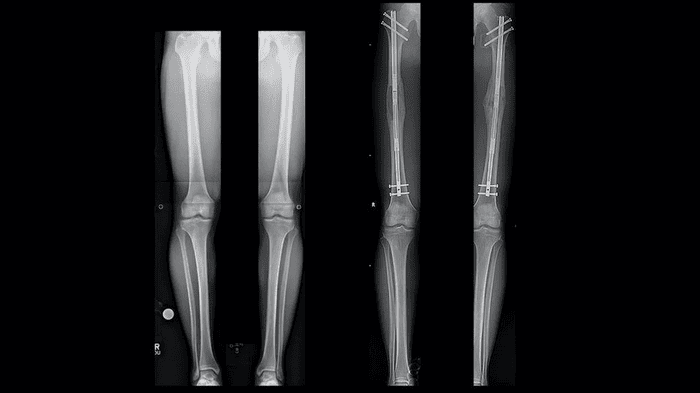

사지연장술을 하는 방법은 우선 환자의 대퇴골을 절삭한 뒤 뼈 사이에 금속 막대를 삽입하고 막대를 하루에 아주 작은 길이로 조금씩 늘려가면서 수술받은 환자의 키를 키울 수 있게 만드는 방식인데요.

수술의 기본적인 원리는 뼈가 다시 붙는 과정에서 뼈를 조금씩 잡아서 늘린다고 생각하시면 되는데요.

이 원리를 이용해서 멀쩡한 다리 뼈를 자른 후에 그 사이에 인공적으로 늘려주는 기계를 삽입한 후 이 기계를 통해서 두 뼈가 맞붙을 때마다 조금씩 길이를 늘려가는 방식인데요.

이렇게 하면서 자연적으로 뼈의 길이가 늘어나게 만들어주는 것입니다.

보통 안정적인 연장 길이는 4cm에 6cm 정도를 말을 하지만 이왕 수술하게 되면 키가 많이 큰 것을 고려하기 때문에 최대 10cm에서 15cm 정도까지도 늘릴 수 있다고 알려져 있습니다.